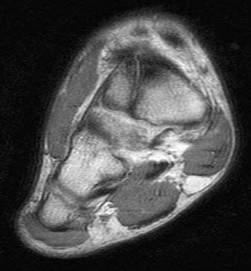

Question 4:

A 55-year-old woman feels a 'pop' in the back of her knee while squatting. An MRI is shown: A posterior horn medial meniscus root tear is identified. Biomechanically, a complete medial meniscus posterior root tear alters contact pressures to a degree equivalent to which of the following?

Correct Answer: Total meniscectomy

Explanation:

A complete posterior root tear of the medial meniscus leads to a complete loss of hoop stresses, resulting in meniscal extrusion. Biomechanically, this alters peak tibiofemoral contact pressures and reduces contact area to a degree equivalent to a total meniscectomy, leading to rapid articular cartilage degeneration.